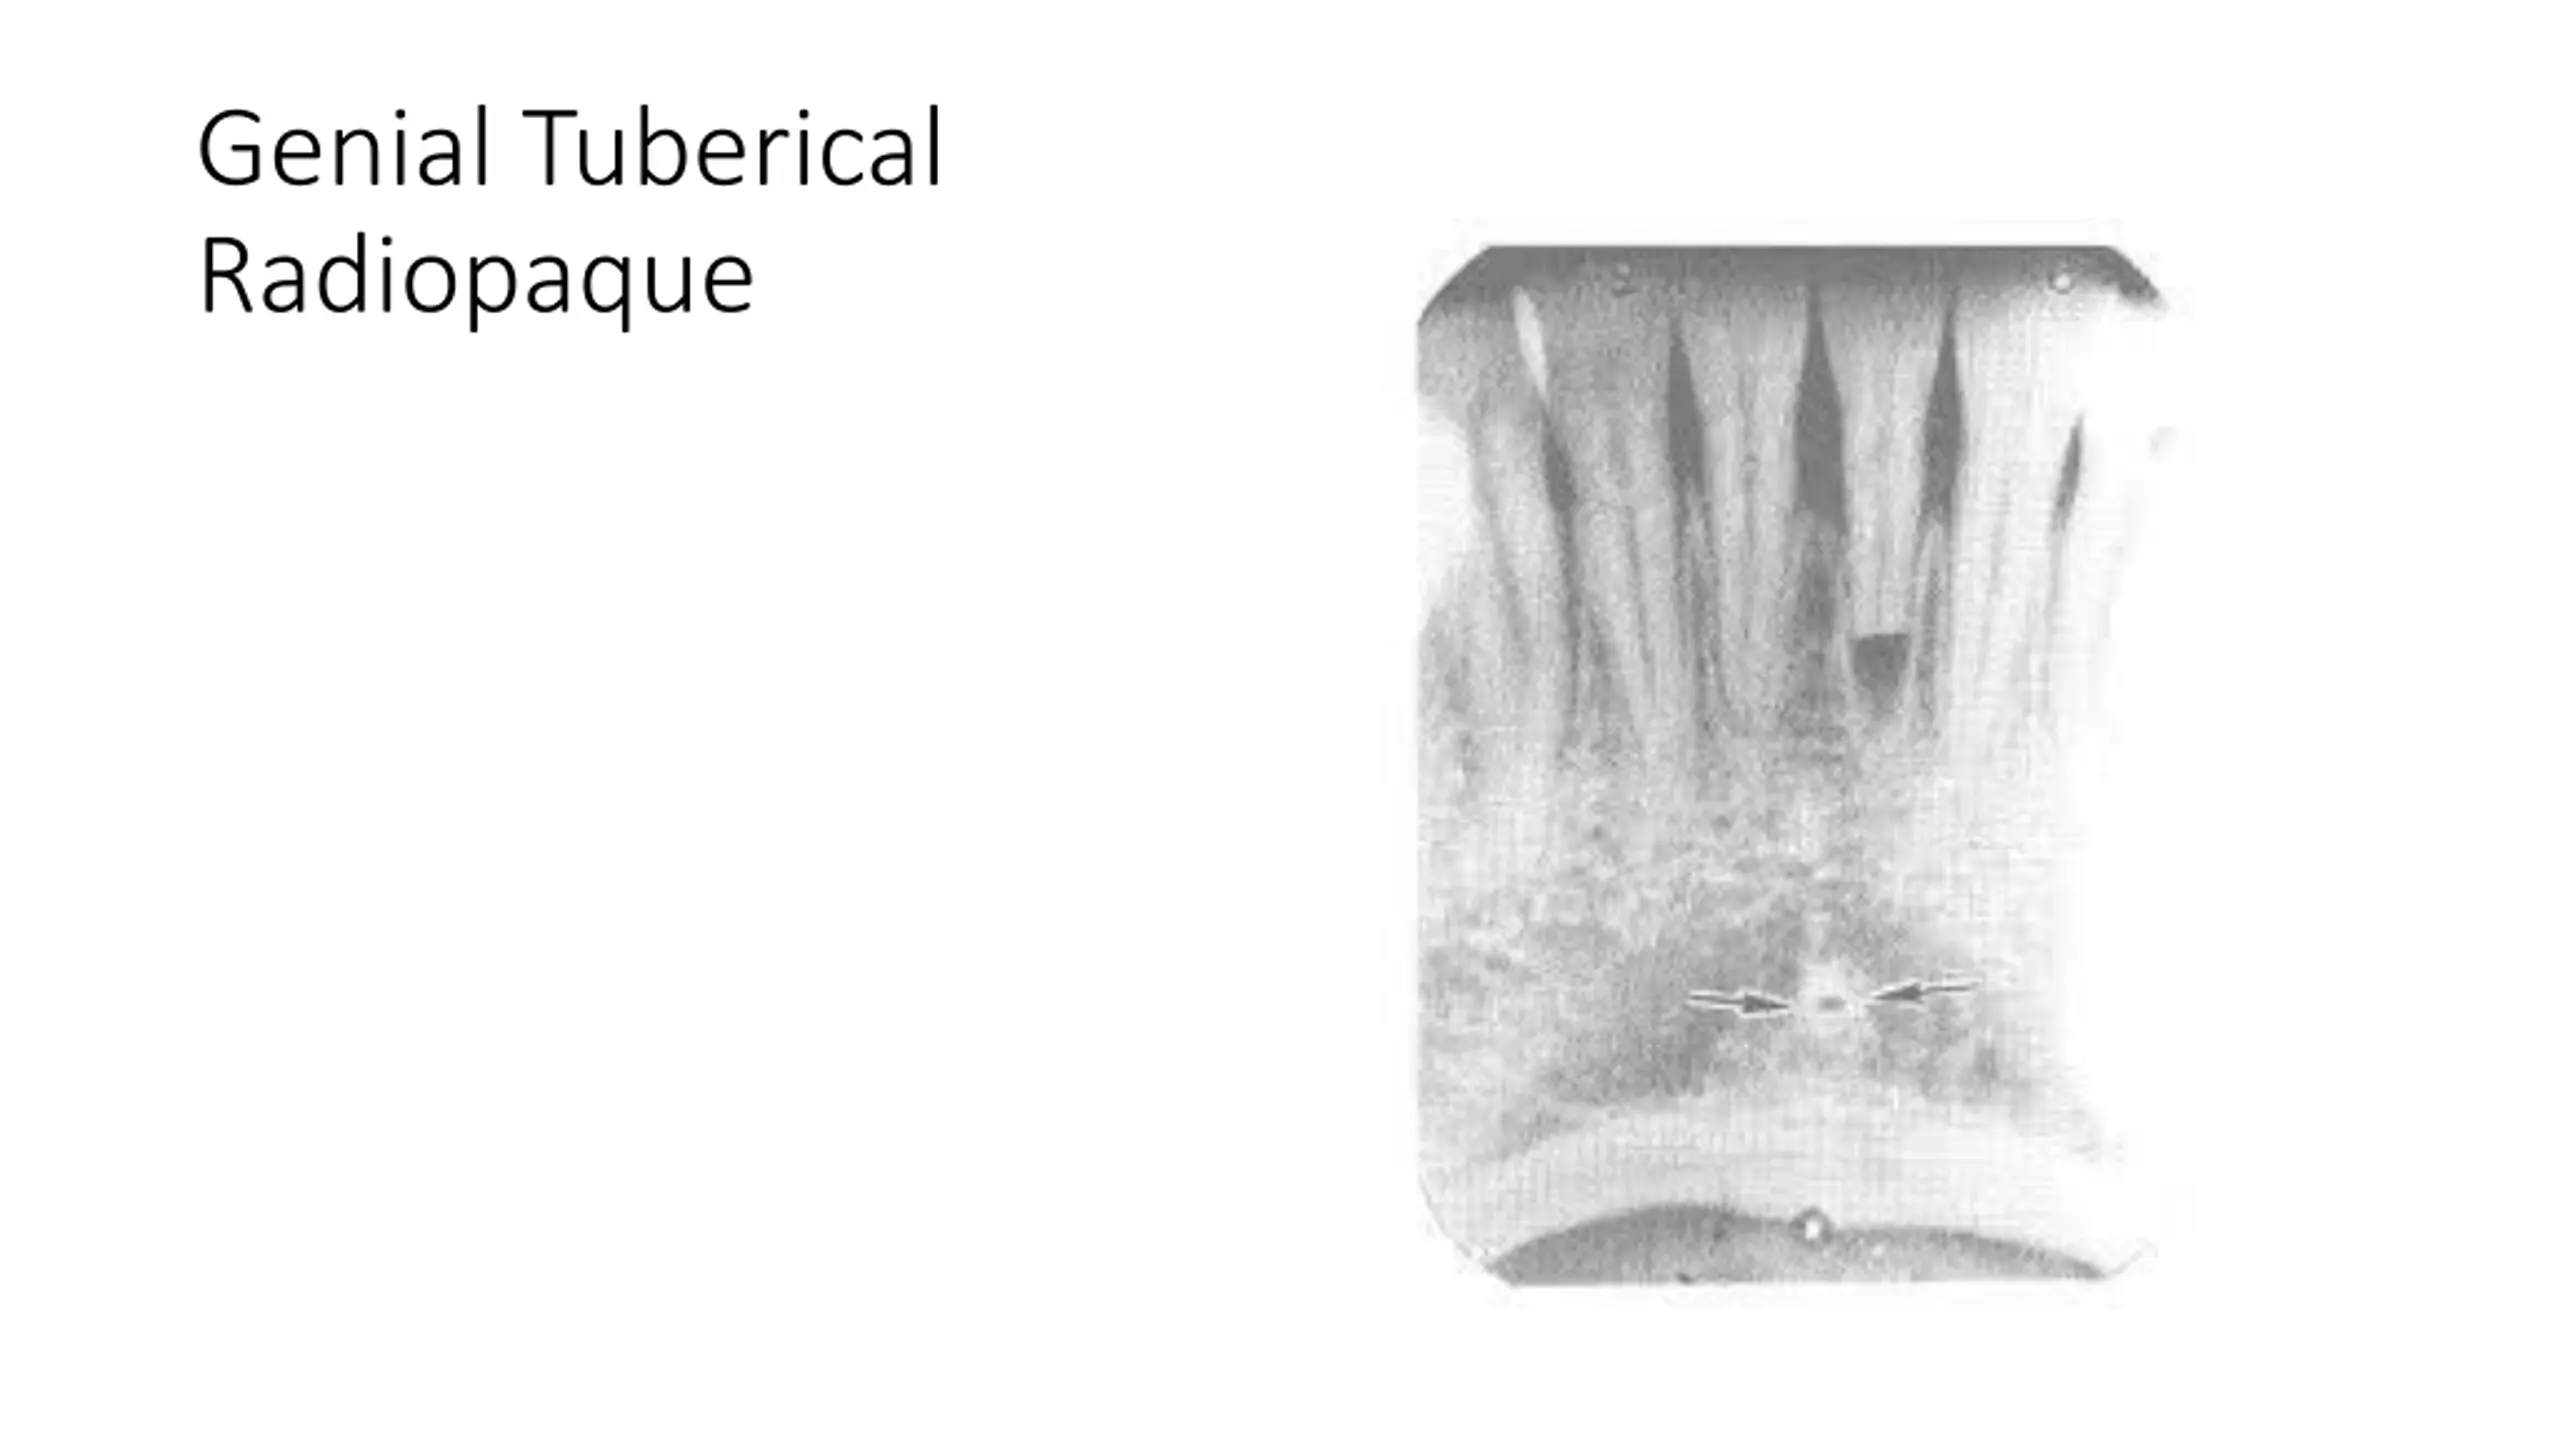

Genial Tuberical Radiopaque